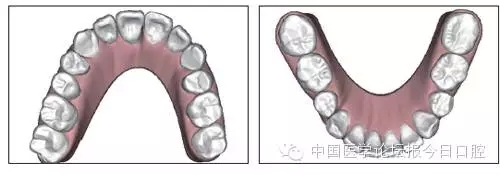

8.webp.jpg

9.webp.jpg

圖5 治療前ODS模型